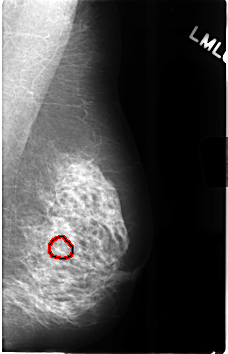

C_0310_1.LEFT_MLO

FILE: C_0310_1.LEFT_MLO.OVERLAY

TOTAL_ABNORMALITIES 1

ABNORMALITY 1

LESION_TYPE CALCIFICATION TYPE AMORPHOUS DISTRIBUTION CLUSTERED

ASSESSMENT 4

SUBTLETY 2

PATHOLOGY BENIGN

TOTAL_OUTLINES 1

BOUNDARY